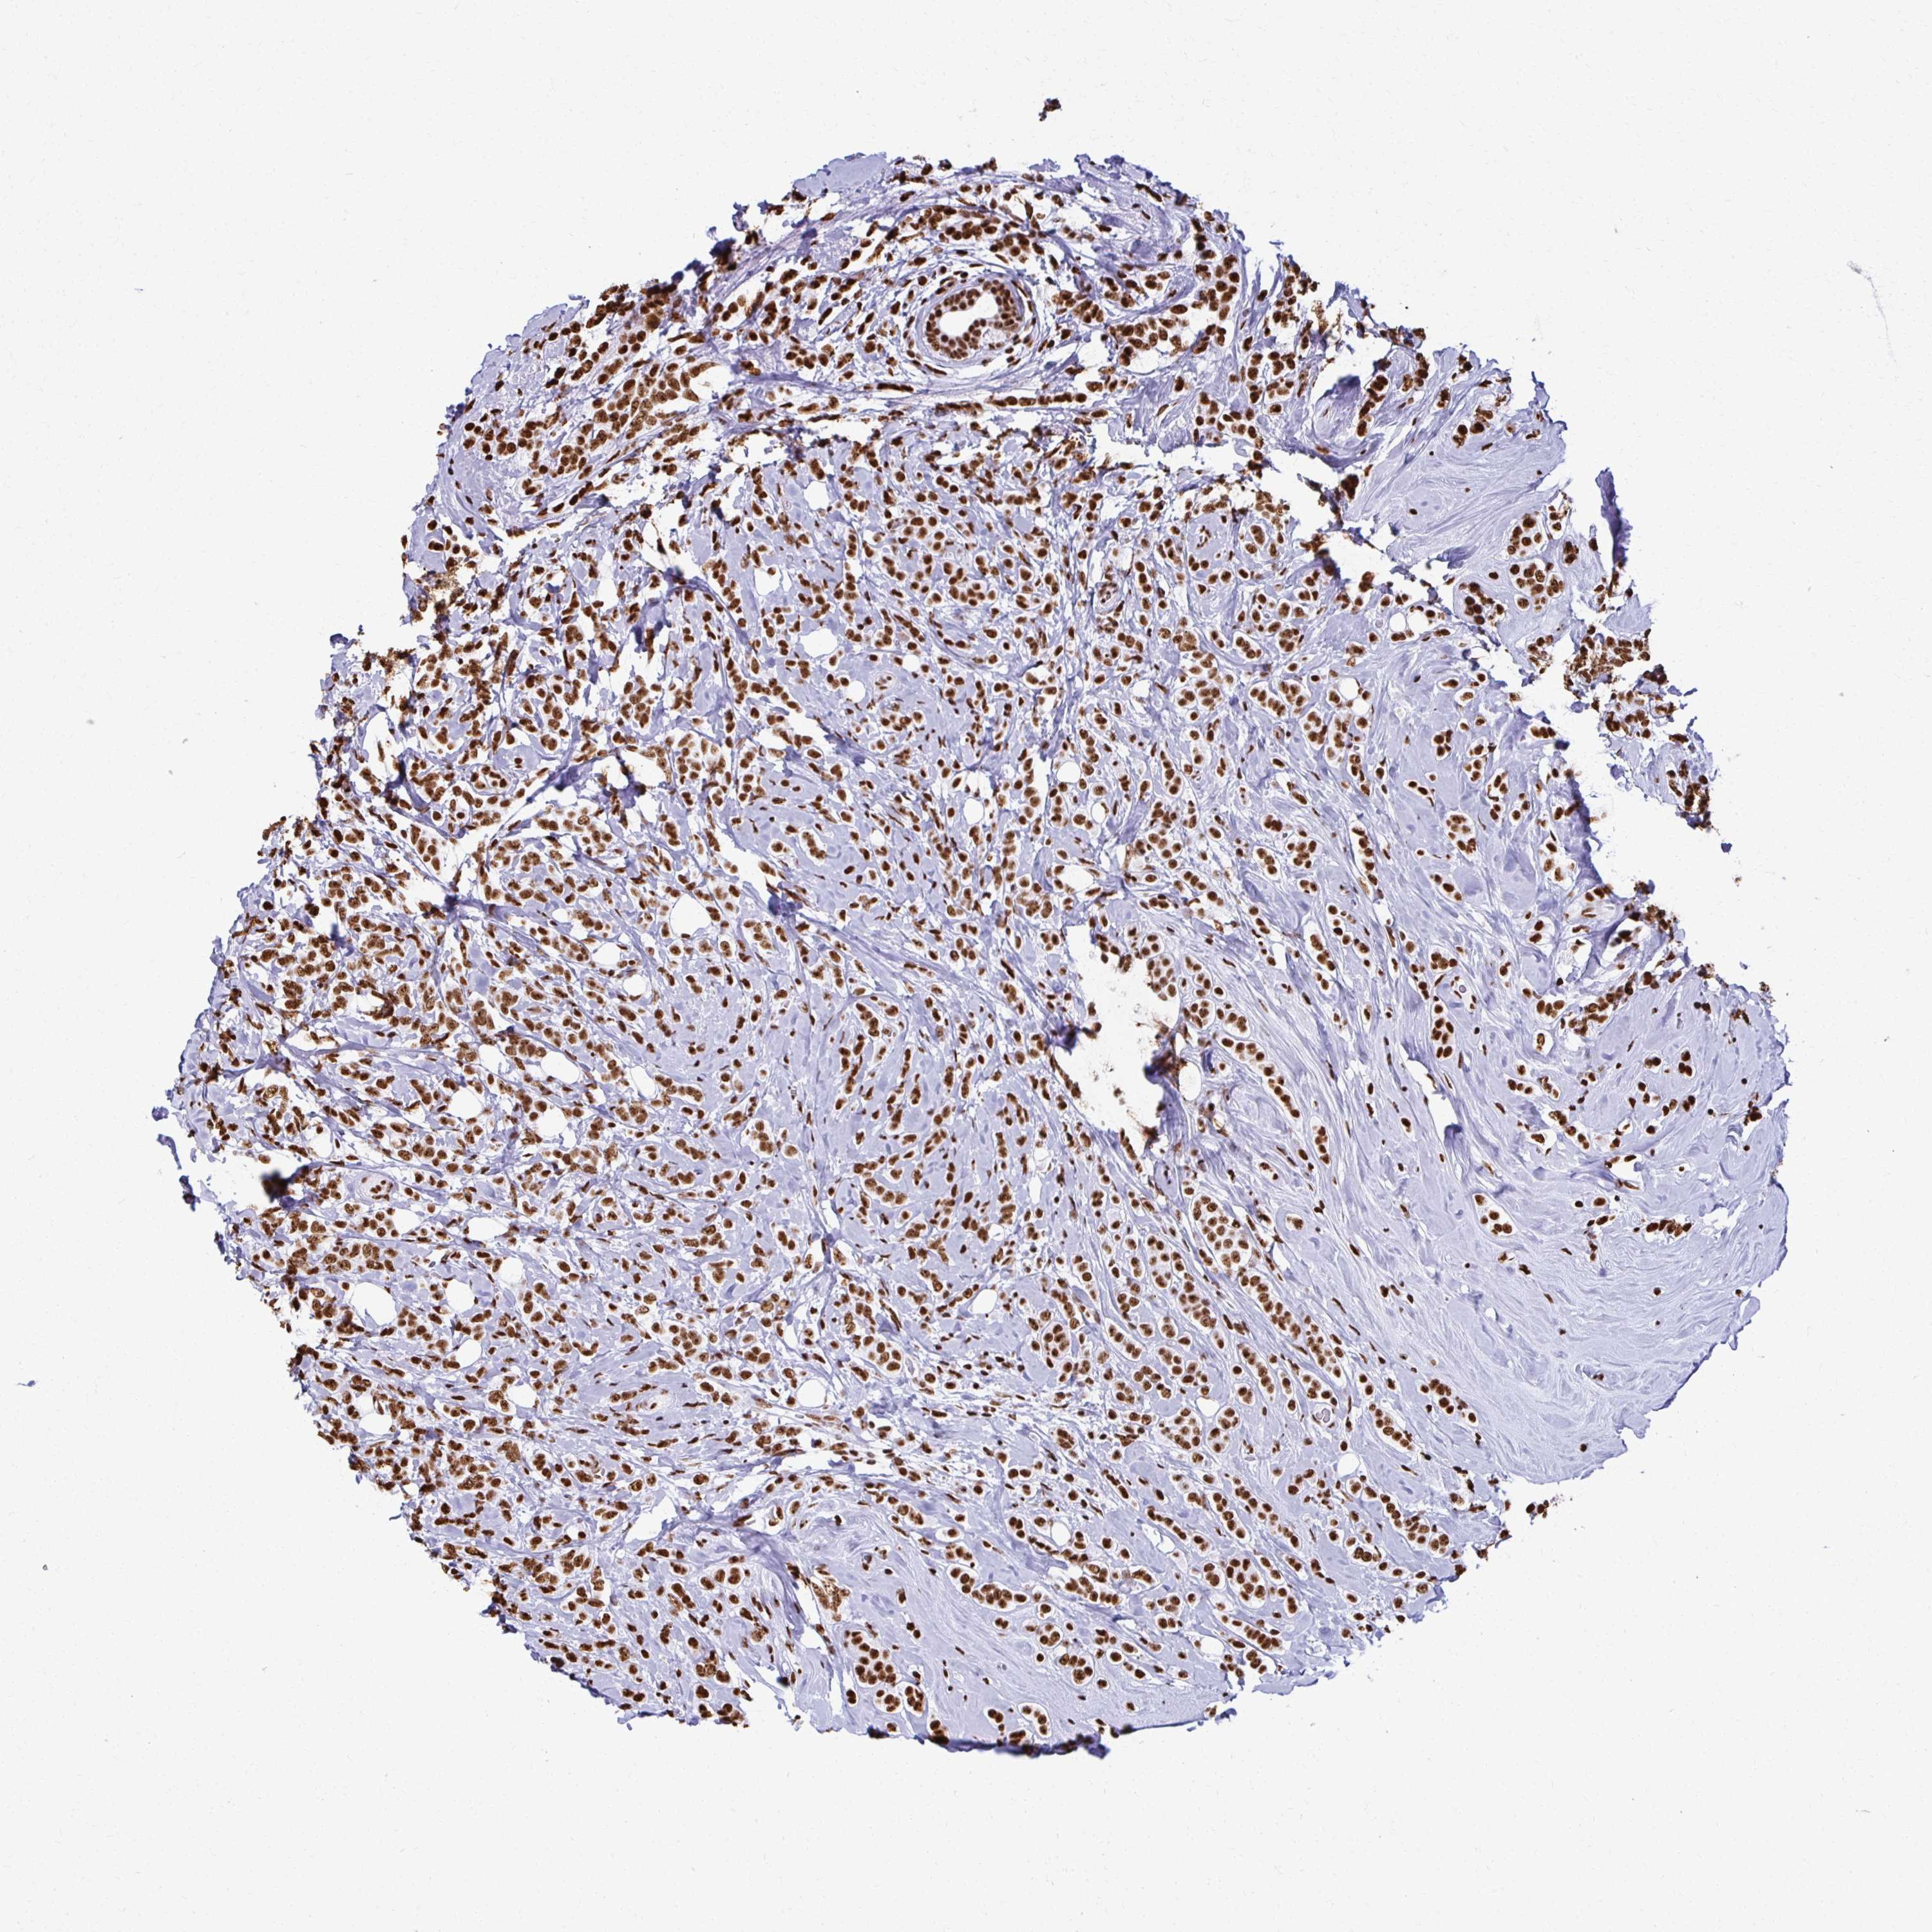

CANCER BREAST CANCER Show tissue menu

BRCA TCGA BRCA VALIDATION PROTEIN EXPRESSION